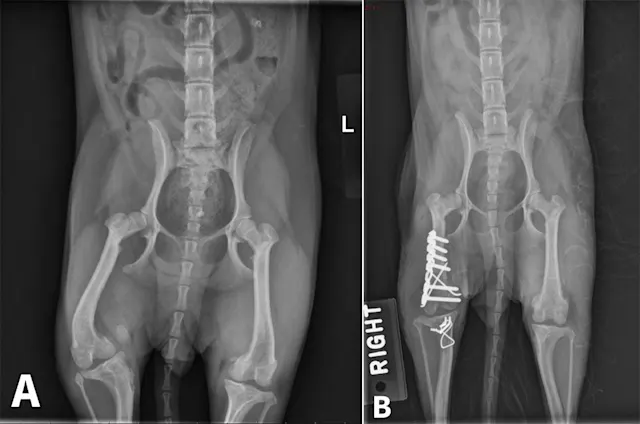

Angular limb deformities (ALD) can occur in both small and large companion animals and can result in significant functional impairment. Although any long bone in dogs can be affected, ALD are most commonly seen in the antebrachium, as well as in the femur and tibia secondary to patellar luxation.1 Deformities may develop secondary to abnormalities in bone growth (eg, premature closure of physis following trauma), bone formation (eg, disease process disrupting normal endochondral ossification; hypertrophic osteodystrophy, retained cartilaginous core, nutritional disorders), or bone healing (eg, fracture malunion).

Physeal trauma is a common cause of ALD, particularly when paired bones are involved. Distal forelimb trauma in immature patients can cause a compression injury (Salter V fracture)2 to the conical-shaped distal ulnar physis, leading to premature closure of the distal ulnar physis. This results in cessation of ulnar growth. Although the radius will continue to grow in affected patients, valgus deviation, cranial bowing of the radius, and torsional deformity can typically develop as a result of the constraining effect of the ulna.3